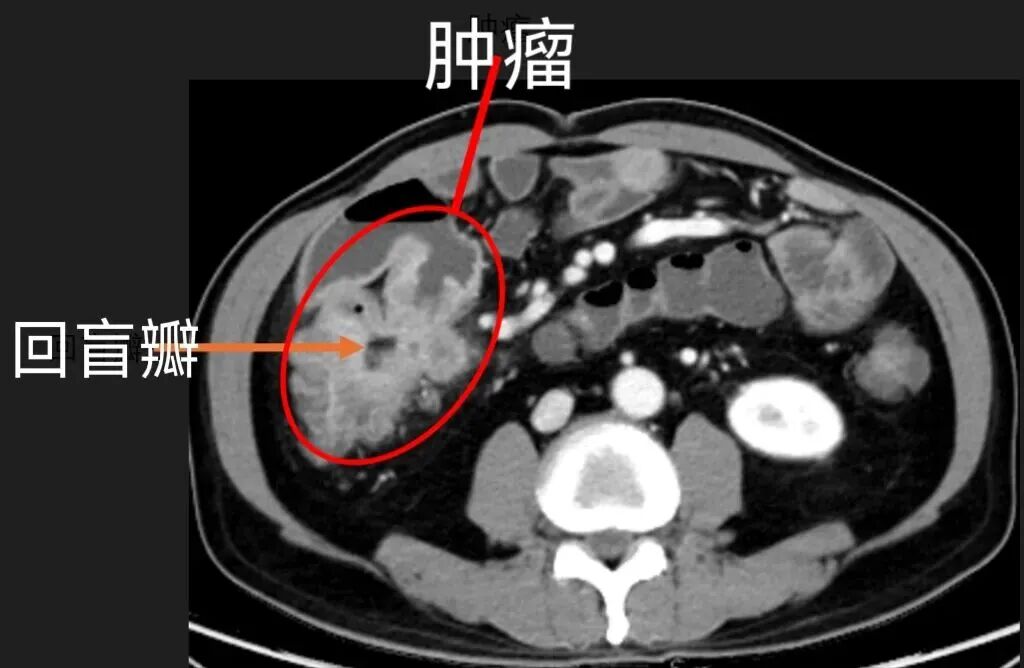

放射诊断科医生凭借丰富经验和细致观察,在张先生的小肠CT薄层重建影像上,敏锐地发现关键隐患:这是一个巨大病灶,长在回盲部,回盲瓣变形了,这种位置的病变很容易被误诊为普通炎症。

更严重的是,影像上肠壁的僵硬感、不均匀强化、周围淋巴结肿大,都指向恶性肿瘤的可能。

张先生重回瑞金医院就诊,多学科专家共同研判并达成共识:患者需尽快手术切除病灶。术中探查发现,患者腹腔存在轻度粘连,5×4cm 大小的肿瘤位于回盲瓣的小肠侧,已侵犯肠壁外层,且与十二指肠紧密相邻,手术需格外精细精准。